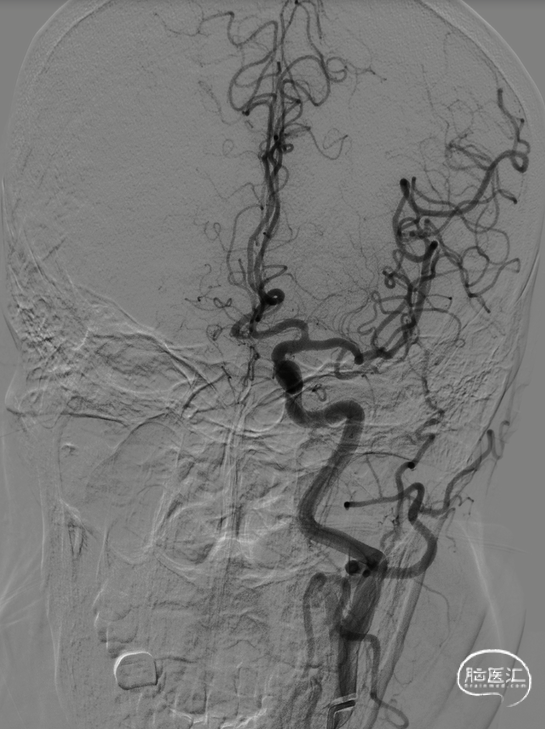

8F导引导管在多功能管及泥鳅导丝导引下直接进入右侧颈总动脉,此时Skathi远端通路导管尾端连接自制50ml负压注射器一路裸奔抽吸至C5段,反复抽吸3次,抽出大量血栓,回血通畅后,轻轻冒烟提示颈内动脉通畅,大脑中动脉M1远端闭塞,与取栓前后循环造影显示情况一致。

大脑中动脉M1段血栓采用SWIM技术-抽拉结合,避免血栓逃逸。

一次SWIM取栓,成功血管再通,达到mTICI分级:3级。